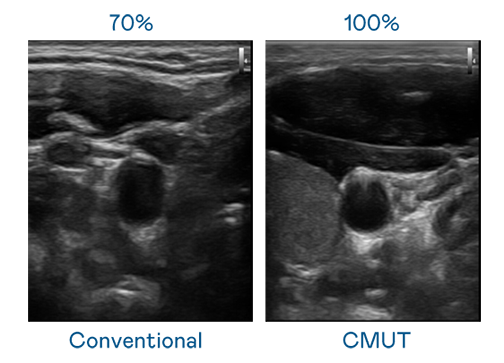

CMUT 技术是一种用电容式微机电元件来产生超音波讯号的技术。与传统 PZT 压电式技术相比,CMUT 频宽增加 30%,更宽频的超音波讯号让影像解析度大幅提升,是实现高影像品质医疗超音波扫描、促进精准医疗发展的关键技术。

超音波影像的解析度高低,首先取决于探头能发出的讯号频宽。royal皇家88 CMUT 可提供高清晰的超音波讯号,提供高频宽、高灵敏度、影像纹理细节更高的超音波影像,协助医护人员缩短影像判读时间及利用精准的医疗影像进行诊断。